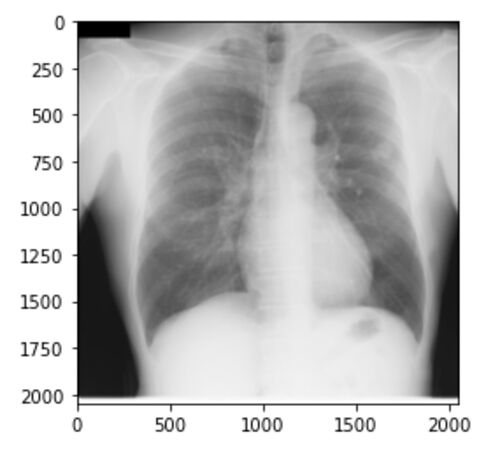

こんにちは!こーたろーです。 本日は、CNNを使って医療画像の分類をやってみました。 難易度は初級です。 前回はDICOMデータを使い、大変な思いをしましたが、今回はpng形式の画像データなので、少し楽になります。 データのダウンロードから、CNN構築・評…